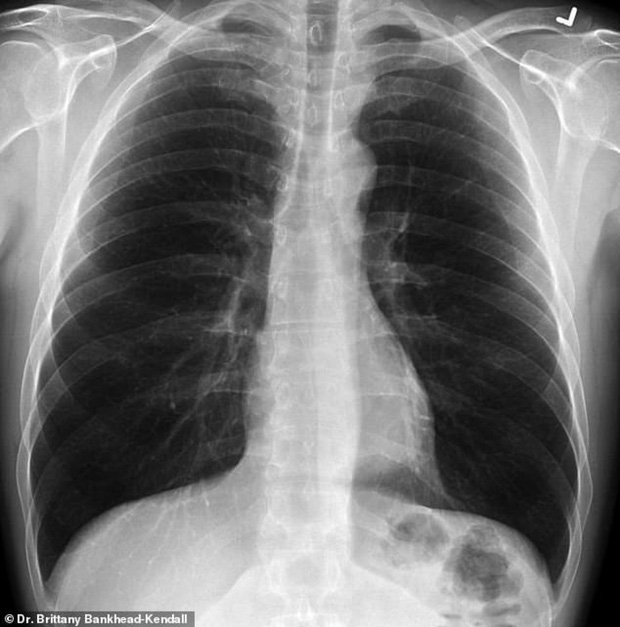

Bác sĩ phẫu thuật Brittany Bankhead-Kendall ở Trung tâm Khoa học Sức khỏe Đại học Kỹ thuật Texas (Mỹ) mới đây trưng ra 3 tấm phim chụp X-quang: Một của bệnh nhân khỏe mạnh, một của người hút thuốc, và một của bệnh nhân Covid-19.

Phim của người khỏe mạnh có nhiều khoảng đen, cho thấy họ có thể hít vào đủ lượng oxy cần thiết. Phim chụp phổi người hút thuốc thì có nhiều khoảng mờ, còn của bệnh nhân Covid-19 thì gần như trắng xóa.

Phổi người hút thuốc (bên trái) và phổi bệnh nhân Covid-19 (bên phải). Ảnh: Bác sĩ Kendall.

Phổi khỏe mạnh. Ảnh: Bác sĩ Kendall.

Những khoảng mờ trên phim chụp phổi thường là chỉ dấu của dịch lỏng, vi khuẩn, hoặc tổn thương và vết sẹo.

Bác sĩ Kendall đánh giá, phổi của các bệnh nhân trải qua Covid-19 tệ hại hơn bất cứ người nghiện thuốc lá nào mà bà từng biết.